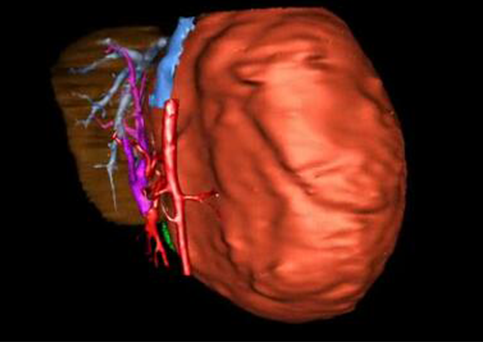

目前常用的检查方法有B超检查、CT、MRI、血管造影等。与其它的腹部肿块的诊断不同,对于小儿肝母细胞瘤血管造影具有重要的意义,可以作为手术前介入治疗的手段,也可为手术提供非常有效的影像学指导,但技术要求高,操作较复杂,且给患儿带来一定的痛苦。近年借助计算机辅助手术系统进行CT原始影像三维重建、手术规划和计算机虚拟手术技术,为精准肝脏手术提供了极为有效的技术支持。

近年来由于数字医学的发展,基于可视化三维重建技术的计算机辅助手术系统极大推进了小儿肝脏肿瘤的精准手术的进步。可以立体透视肝脏解剖、精确掌握肝段的边界、精确测算肝段乃至任意血管所支配的功能体积、准确定位病灶及其与邻近血管的解剖关系,最终对不同手术方案进行比较、筛选和优化。因此,计算机辅助手术规划系统是实现精准肝切除的有力辅助工具,是未来数字外科、精准外科等21世纪外科新理念的重要技术支撑。

计算机辅助手术规划系统具有良好的操作可行性、计算准确性和三维显示效果,可半透明、交互式显示真实的肝内立体解剖关系和空间管道变异,准确计算肝内管道的直径、走行角度,两点间的垂直距离,和任意血管的支配或引流范围等传统二维影像无法获取的信息,有助于实施个体化手术,提高了手术的确定性、预见性和可控性。计算机辅助手术规划系统可直观显示预留肝脏的结构和功能,并可通过虚拟切割功能辅助术者对手术方案进行蹄选和优化,系统评估手术风险和制定对策,改变了部分二维规划的术式和切除范围,使部分二维规划认为不能切除的患者成功手术,提高了手术的根治性、安全性和病变的可切除性,更加符合精准肝脏外科的术前规划要求。详见第11章。

随着计算机技术及影像检查技术的不断发展,以精确的术前影像学和功能评估、精细的手术操作为核心的精准肝切除技术日益受到重视。基于数字医学的计算机辅助手术技术(computer-assisted surgery,CAS)则是实现肝脏精准手术操作的基础。计算机辅助手术系统(CAS)可将术前二维(two dimensional,2D)的CT/MRI影像数据进行三维(three dimensional,3D)重建,建立个体化的肝脏三维解剖模型,清晰显示肝脏内脉管系统的走行及解剖关系,还原病灶与其周围脉管结构的立体解剖构象,准确地对病变进行定位、定性和评估,制定合理、定量的手术方案,实施个体化的肝脏血管取舍分配方案及实施精准肝脏手术。一般认为CAS包括:创建虚拟的患者的图像;患者图像的分析与深度处理;诊断、手术前规划、手术步骤的模拟;术中实时导航。应用本技术后,由于可以更清晰地看出肿瘤的界限,特别是根据肝血管的显影,判断出肿瘤与门静脉及肝静脉的关系以在手术前较准确地估计出手术成功切除的可行性。以往部分根据普通强化CT判断无法手术的病例而被评估为可以成功切除并手术成功。